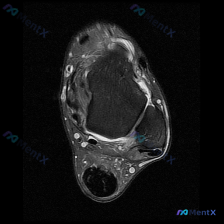

踝关节MRI看到少量软组织积液,到底要不要紧?这里梳理了完整分析思路

今天整理了一份踝关节MRI的读片分析,核心问题是影像发现「软组织积液」该怎么判断,分享出来大家一起讨论。

这是一份踝关节轴位T2加权MRI(T2WI)的读片报告,核心信息整理如下:

- 骨骼结构:胫骨远端、距骨骨髓信号正常,无骨髓水肿、骨质破坏,皮质完整,未见骨折线

- 关节结构:胫距关节间隙清晰,关节腔内可见少量T2高信号液体;关节软骨轮廓清晰,无明显软骨缺损

- 肌腱韧带:所有可见肌腱走形连续,信号均匀,无增粗、断裂或异常高信号;各腱鞘无异常积液;区域内韧带连续性良好,无肿胀断裂

- 软组织与血管神经:皮下脂肪、筋膜结构清晰,无弥漫性水肿或肿块;踝管区神经血管束走行自然,无压迫征象

核心总结:仅发现踝关节腔内少量液体信号,其余所有结构均未见明显异常,无占位、无骨质破坏。